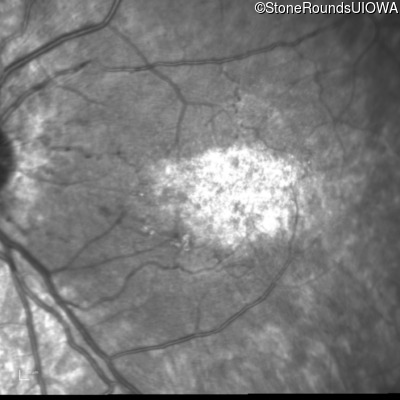

Infrared Fundus Photograph - Right - 20/160

Exemplar